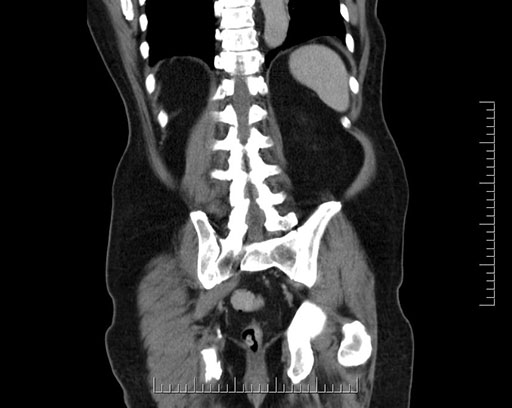

Whipple (pancreaticoduodenectomy) [case 7]

Imaging Analysis

Look through the patient's CT scan to identify any areas of concern for the necessary procedure.

Based on your CT findings, which issue(s) would give reason for "planned slowing down moment(s)" in this case?

Considering a standard Whipple procedure, what step(s) of the operation would you do differently in this case?